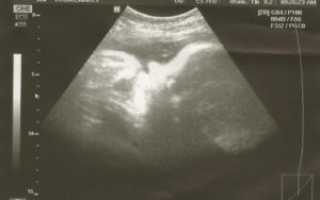

Обычно все плановые ультразвуковые исследования уже сделаны. УЗИ на 39 неделе беременности назначается только в случае уточнения веса и роста плода, развития его органов и систем, а также для определения тактики ведения родов. Внимание уделяется состоянию шейки матки, степени зрелости плаценты, а также тому, есть ли обвитие пуповиной или нет.

Врач проводит полный осмотр беременной: определяет предлежание плода, подвижна или нет головка плода над входом в таз, определяет массу плода и оценивает состояние шейки матка.

Шейка матки на 39 неделе уже начинает укорачиваться и размягчаться, кроме того после отхода слизистой пробки она потихоньку раскрывается. В норме раскрытие шейки до начала родов на 1 см.

На 39 неделе женщине нужно быть очень внимательной к своим выделениям. На этом сроке возможно преждевременное излитие околоплодных вод. Если выделения стали обильнее, обратите внимание на их консистенцию.

В случае появления водянистых выделений нужно срочно обращаться к доктору. Подтекание вод может быть малым, что совершенно не страшно, а может быть обильным.

В таком случае может быть принято решение об экстренном родоразрешении.